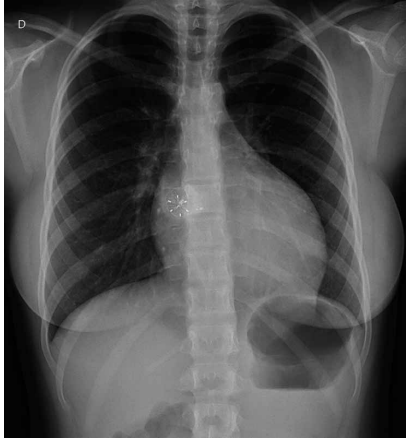

Paciente de 1 ano e 1 mês veio encaminhada, via

CROSS, por cardiopatia congênita. A avó refere que a

criança, desde os 2 meses de idade, fica com a boca roxa

quando chora. Lembra de ter levado a uma UPA, sendo

auscultado um sopro na ocasião e aferida saturação periférica de oxigênio em ar ambiente de 98%. Avó refere,

também, sudorese importante e cansaço às mamadas

com dificuldade de ganho pondo-estatural, além de infecções respiratórias frequentes.

(Arquivo pessoal; imagens usadas com autorização)

Diante do exposto, o diagnóstico correto é: